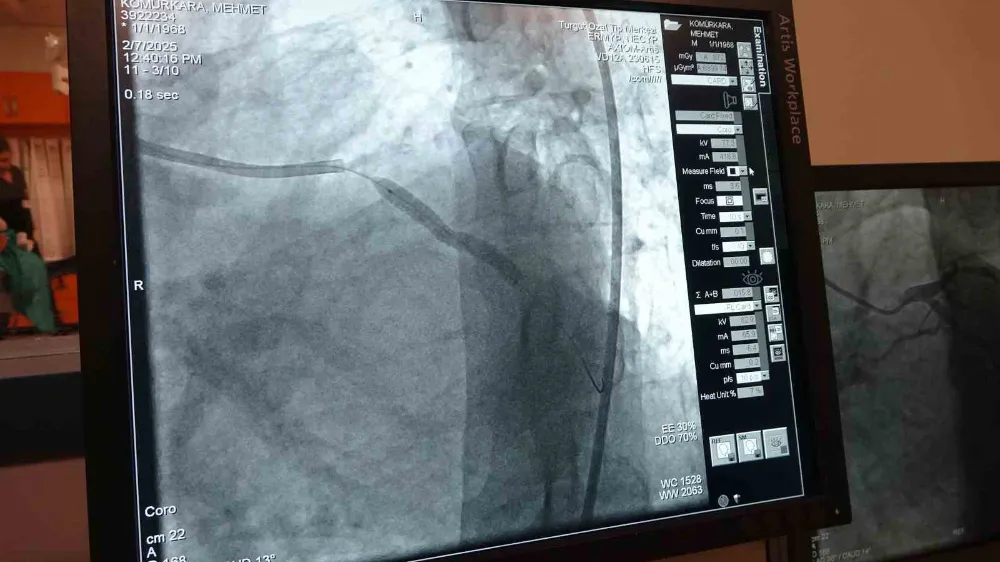

Prof. Dr. Pekdemir, koroner damarların ani tıkanmasının kalp krizi ile sonuçlandığını ve acil müdahale gerektirdiğini söyledi. "Koroner damarlar zamanla daralabilir, ancak bazı durumlarda bu daralmalar yıllarca belirti vermeden ilerleyebilir. Bu duruma kronik total oklüzyon (CTO) denir" diyen Pekdemir, CTO’nun yaygın bir durum olduğunu vurguladı.

Pakdemir, "Bazen kalbin bir damarında 2 damarında ortaya çıkabilir damarın tıkandığı bölgenin altında beslenemeyen yerlere vücut ince küçük damarlar geliştirebilir biz buna kollateral damarlar diyoruz normalde istirahatle hemen gezse bile hastaya günlük aktivitesinin bize ya da bir efor sarf ettiğinde bunlar yetmez. Bu durum yeterli olmayınca bazen şikayetlere yol açar en büyük şikayetlerinin işte eforla gelen nefes darlığı çarpıntı göğüs ağrısı bazen öyle bir hale gelir damarlar tam oluşmadığı zaman tam gelişmediği zaman dinlenme dahi günlük aktivitelerini yaparken dahi hatta göğüs ağrısı ve nefes darlığı şikayeti olur. Kronik total oklüzyon (CTO)dediğimiz damarlar genellikle her anjio olan her 5 hastadan birinde bulunur yaşla yaşlılıkla giderek sıklığı artar yani 65 yaşının üstünde yüzde 40’larda iken yetmişli 80 yaşları geçtiğimiz zaman bu oran yüzde 40- 45’e kadar yükselir. Damarın içerisindeki darlığın yapısı doğası çok sert bir yapı olduğu için anjio ile girdiğimizde daha değişik geliştirilmiş kompleks malzemelerle ve değişik tekniklerle açmak zorunda kalıyoruz. Normalde hastanın iki kasığını kullanarak 2 kateteri yerleştiriyoruz ve sert kesici teller mikro kateterler ona özel geliştirilmiş balonlar ve destek kateterleriyle bir taraftan tıkalı damara müdahale ederken bir taraftan da alt tarafının görüntülenmesini sağlıyoruz. Bu işlem deneyimli bir merkezde yapıldığı zaman dünya çapında yüzde 70 başarısı vardır. Klinik olarak Türkiye’de bu işi en iyi yapan merkezlerden biriyiz" diye konuştu